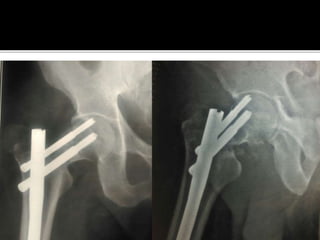

If neither have been followed, it is not right to

blame the nail or the device or to look for a new

design

Factors in our control:

1. Correct choice of implant

2. Correct execution of surgery